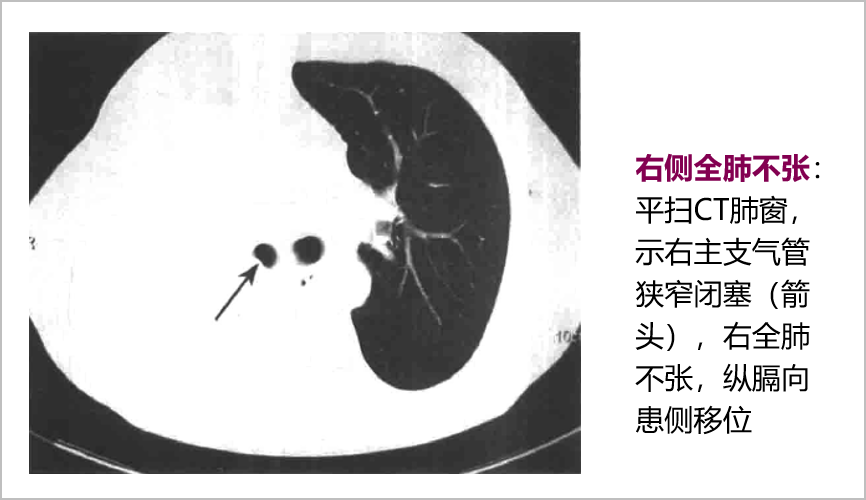

胸膜疾病影像表现